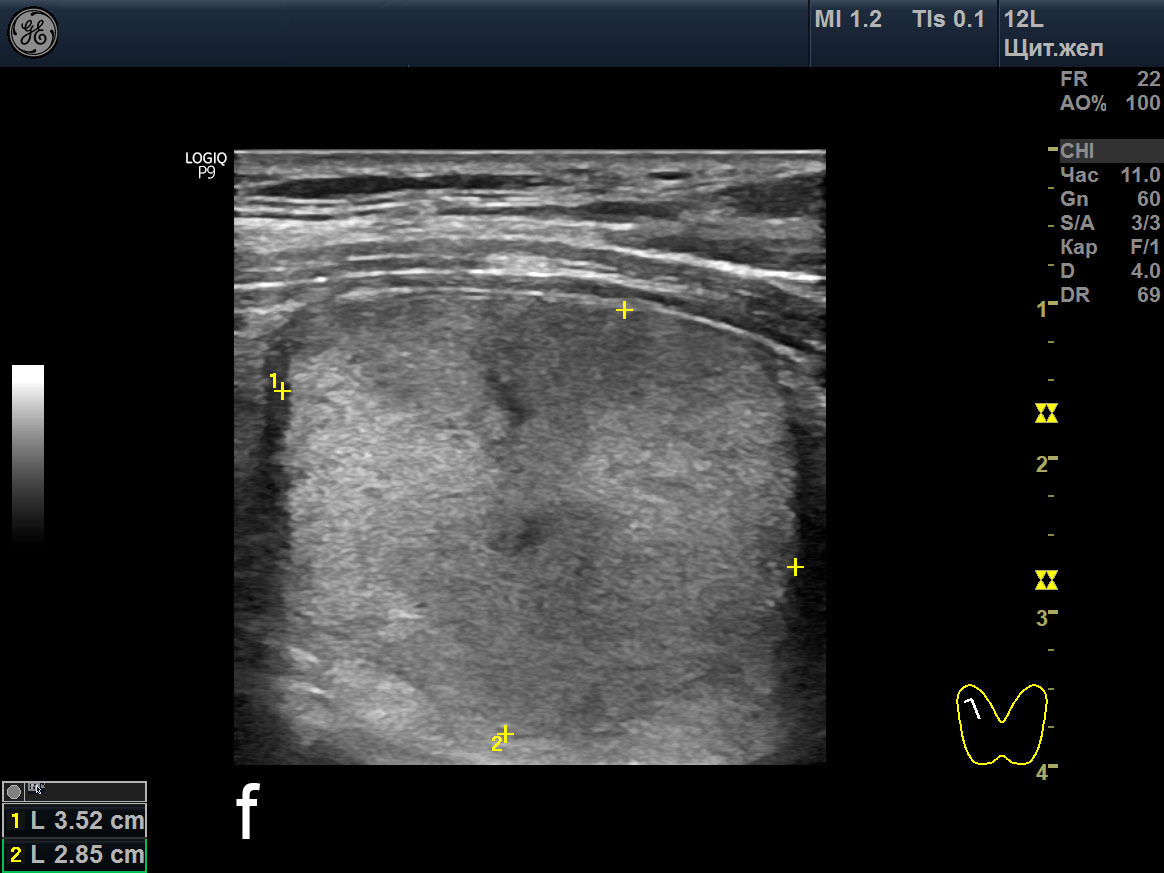

Теплый узел щитовидной

Теплый узел щитовидной 107 фотографий